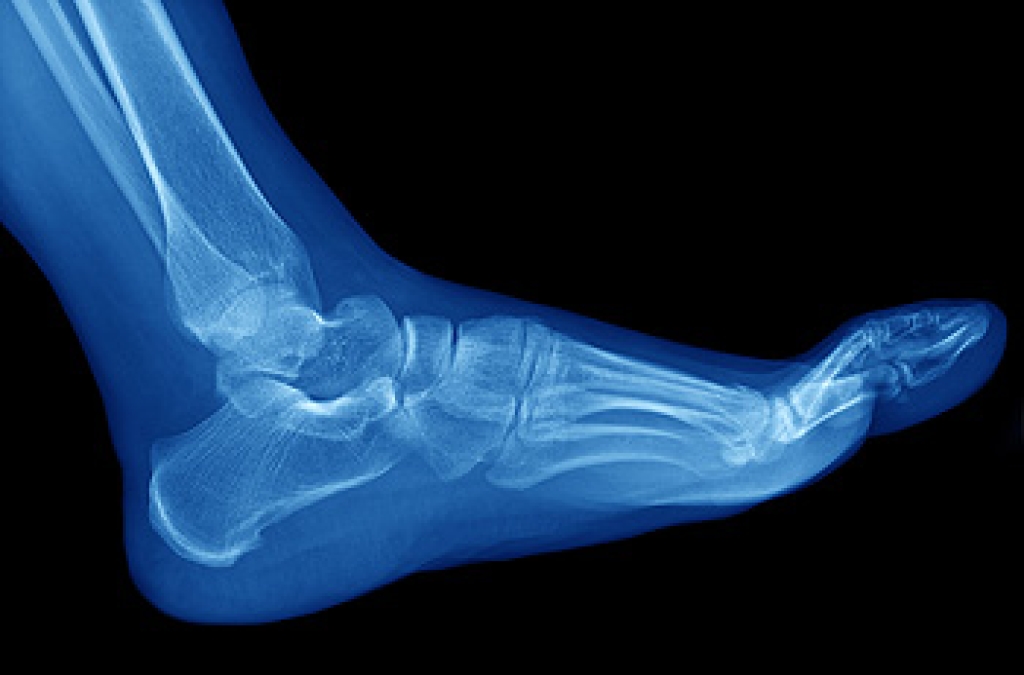

Diagnosis of cuboid syndrome is often difficult, and it is often misdiagnosed. X-rays, MRIs and CT scans often fail to properly show the cuboid subluxation. Although there isn’t a specific test used to diagnose cuboid syndrome, your podiatrist will usually check if pain is felt while pressing firmly on the cuboid bone of your foot.